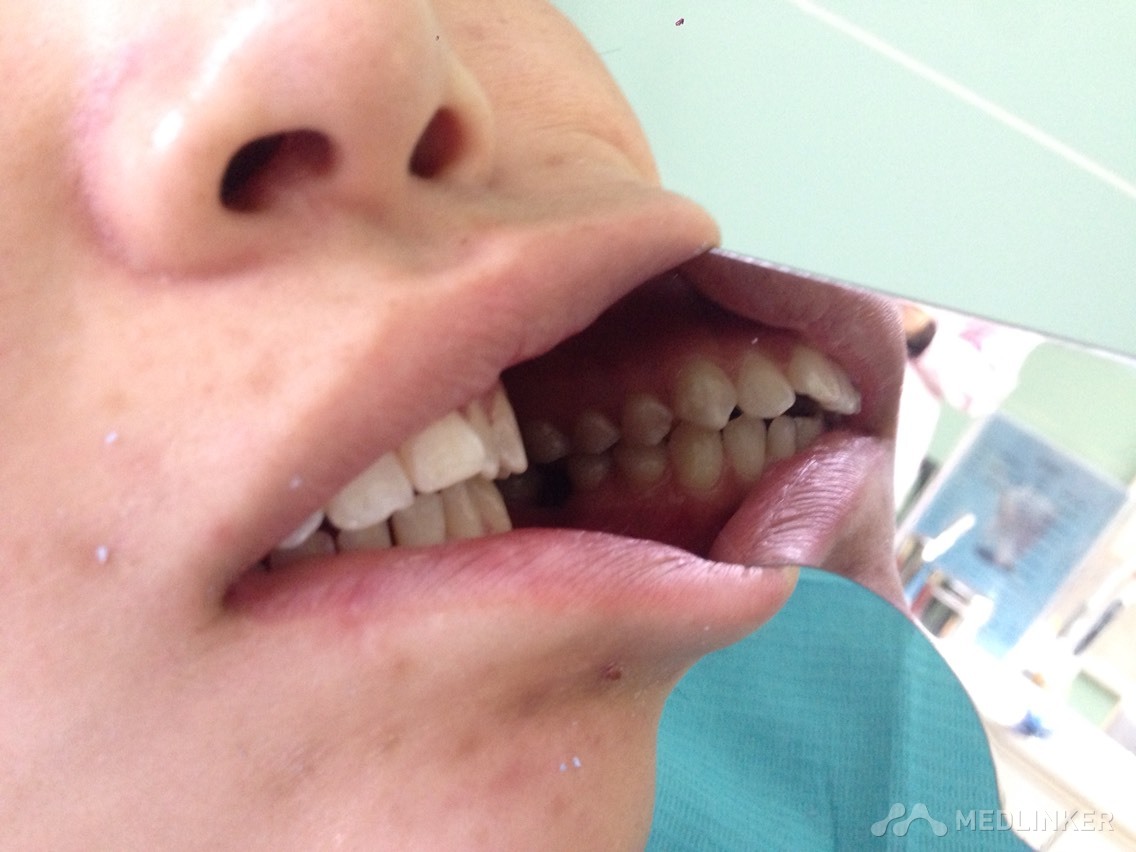

患者女,23岁,想做隐形无托槽矫正

上颌前牙牙列拥挤,下颌前牙散在间隙,下颌双侧第一磨牙缺失多年,开合